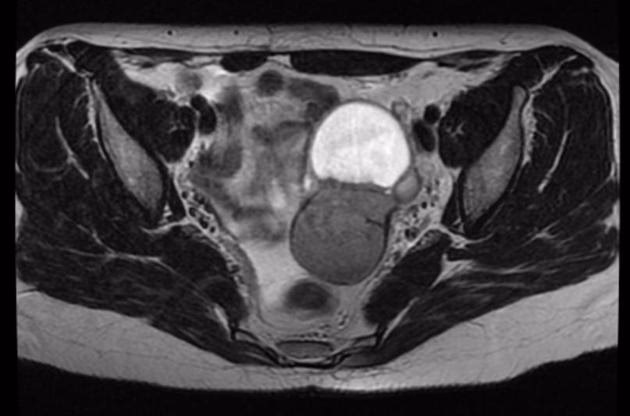

Magnetisk Resonansscanning (MRI): Et Detaljeret Kort over Bækkenet

MR-scanning er en anden kraftfuld billeddiagnostisk metode, der ofte anvendes som et supplement til TVUS, især i komplekse tilfælde eller som en del af den præoperative planlægning. En MR-scanning giver et fremragende overblik over hele bækkenet og kan visualisere væv og organer med meget høj kontrast.

Specifikke tegn på dyb endometriose på en MR-scanning inkluderer det såkaldte "mushroom cap sign", hvor endometriose i tarmvæggen ligner en svamp, der vokser ind i tarmens muskellag.